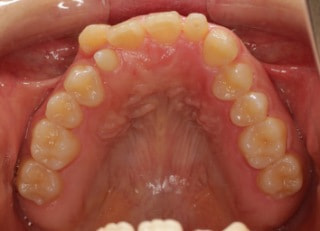

上顎2番矮小歯右下2番先天欠如

解説:下顎前突上顎劣勢長傾向で、上顎両側2番が矮小歯、右下2番先天欠如症例なので、上下前歯の幅径の比率を調節する必要があるケースです。(ご本人のご都合で治療中に来院できない期間がありました)

治療後(2年11ヶ月後)